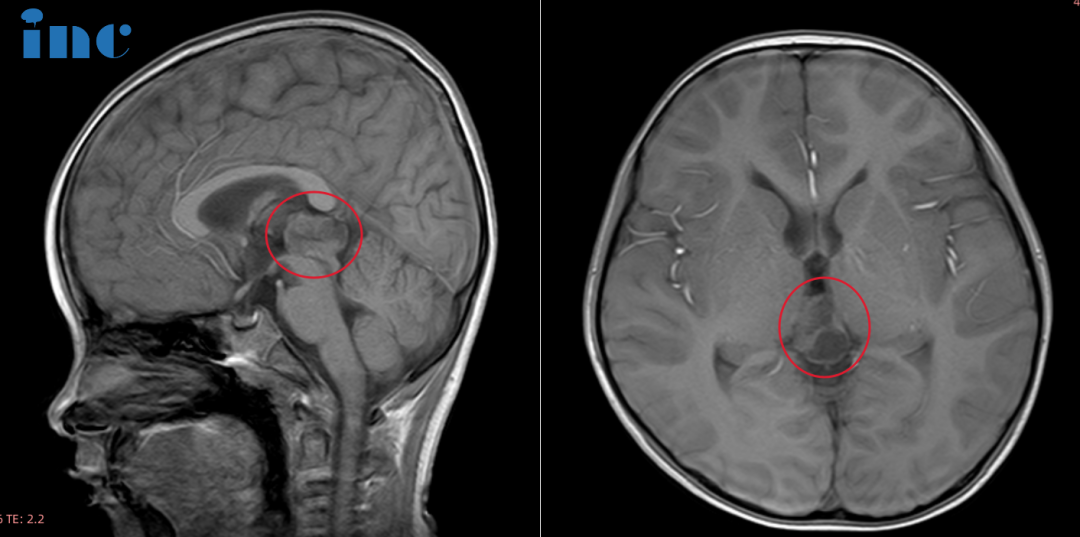

巴教授在北京天坛医院为鑫鑫成功完成了全切手术,术中对神经功能的保护完美无缺。术后第一天,鑫鑫便从ICU转回普通病房,状态良好:能进食、能清晰表达、无疼痛不适,还能握住巴教授的手,四肢活动正常。次日查房时,这位小战士用英语说出了自己最喜欢的玩具"Tank!",稚气的童言让在场的父母和医护人员都露出欣慰的笑容。主刀团队的国内专家也纷纷为他点赞。

为争取更高的生存率,鑫鑫的父母在INC国际神经外科医生集团协调下,寻求巴特朗菲教授进行手术切除。松果体区肿瘤的手术入路一般包括幕下小脑上入路、枕下小脑幕入路、后纵裂经胼胝体入路等,最适合的方式主要取决于肿瘤的解剖学特点。针对鑫鑫的情况,巴特朗菲教授采取幕下小脑上入路,最终实现了肿瘤的全切除,并尽力减少了对周围组织的损伤,这对预防后期肿瘤复发起到了关键作用。